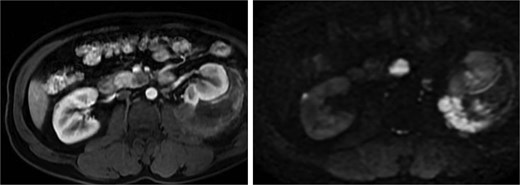

A pancreatic uncinate process mass measured 18 × 20 mm and was hypointense on T1-weighted and mildly hyperintense on T2-weighted imaging, with relative hypoenhancement compared with adjacent pancreatic parenchyma and marked diffusion restriction (Fig. 5). A right adrenal mass measured 12 × 16 mm, was mildly hyperintense on T2-weighted imaging, and showed contrast enhancement and diffusion restriction (Fig. 6). Brain MRI demonstrated no intracranial lesions.

MRI of the pancreatic uncinate process mass showing low T1 signal, mildly increased T2 signal, restricted diffusion, and relative hypoenhancement on post-contrast images.